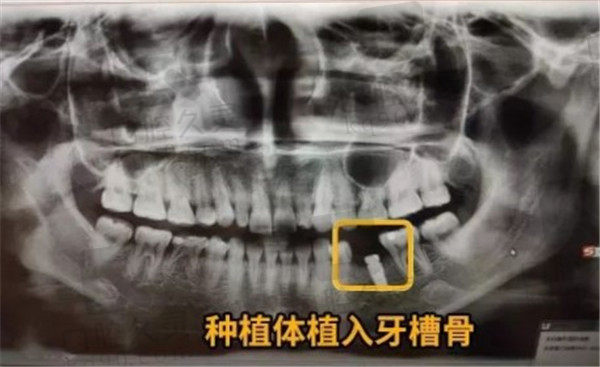

刘院长根据顾客的诉求,已经口腔状况,选择了瑞典诺贝尔种植体+全瓷冠的方式给顾客进行牙齿种植

术后反馈:种植体植入手术全程都是在无菌手术室里进行的,进入手术室经过了消毒,牙齿种植手术全程我被用绿布遮盖,植牙手术期间不太压抑,除了打麻药的时候疼了下,其他时候都很舒适。时间也很短,大概30分钟之后我就拥有了一颗真牙,从外观看诊的很难发现和旁边的牙有什么区别